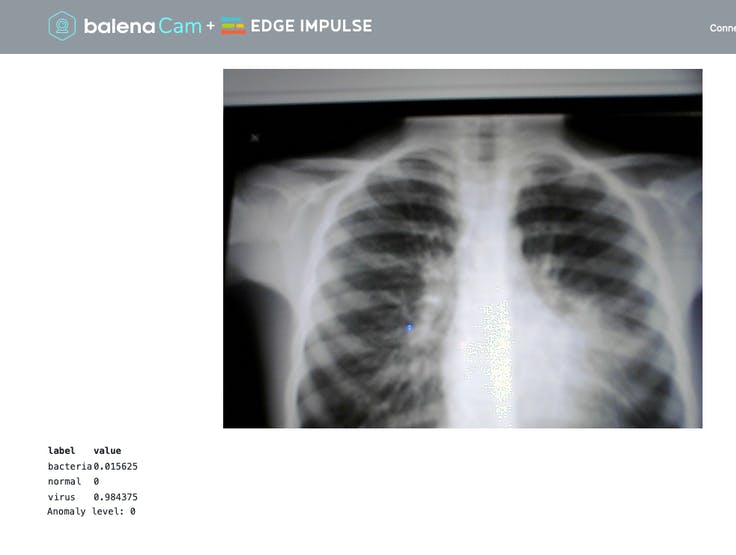

Once the containers are deployed on your device using balena. Enable the Public device URL on your device. Open your browser using the public URL provided by balenaCloud or enter your device’s local IP.

The camera feed should be displayed on the webpage. If you notice slow framerate, probably your web browser doesn’t support WebRTC and your client has switched to MJPEG. You can check the next section to debug WebRTC.

Try to move different objects in front of the camera and see how well the classifier works! Predictions are displayed for all labels with values between 0 and 1, 1 being a perfect prediction.